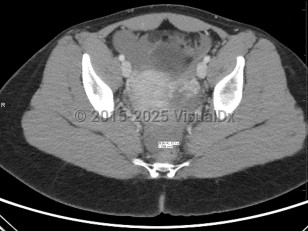

The term ectopic pregnancy refers to implantation of a developing blastocyst at any location outside of the endometrial cavity. Ectopic pregnancies can be found in the cervix, cornua, fallopian tubes, ovaries, or a prior cesarean delivery scar, or, more rarely, attached to the abdominal lining, bowel, or other viscera. The most common location is the fallopian tube, specifically the ampulla, which accounts for about 70%-80% of cases, followed by the isthmus and fimbria. Prevalence is estimated at 25 in 1000 pregnancies, with fewer than 200 000 cases in the United States per year. It is a medical emergency.

Presentation can vary. Patients may present with a positive home pregnancy test and unilateral lower quadrant pain that is often sharp / stabbing in nature. Some will present after tubal rupture and be hemodynamically unstable. Others may present with only vaginal spotting and be unaware they are even pregnant. Therefore, one must have a high index of suspicion when a patient arrives with a positive pregnancy test and symptomatology. As many as 18% of women presenting to the emergency department with first-trimester bleeding, pain, or both will be found to have an ectopic pregnancy.

Ruptured ectopic pregnancy can result in intraperitoneal bleeding, uterine hemorrhage, and hemodynamic instability. Development of any of these complications should be considered a surgical emergency and warrants emergent evaluation by a gynecologic surgeon; exploratory laparotomy may be required. Even in the absence of concern for rupture, surgery may be considered, particularly in patients failing or with contraindications to methotrexate, in the setting of heterotopic pregnancy (ectopic pregnancy occurring simultaneously with a viable intrauterine pregnancy; see Look For), or in patients seeking sterilization.